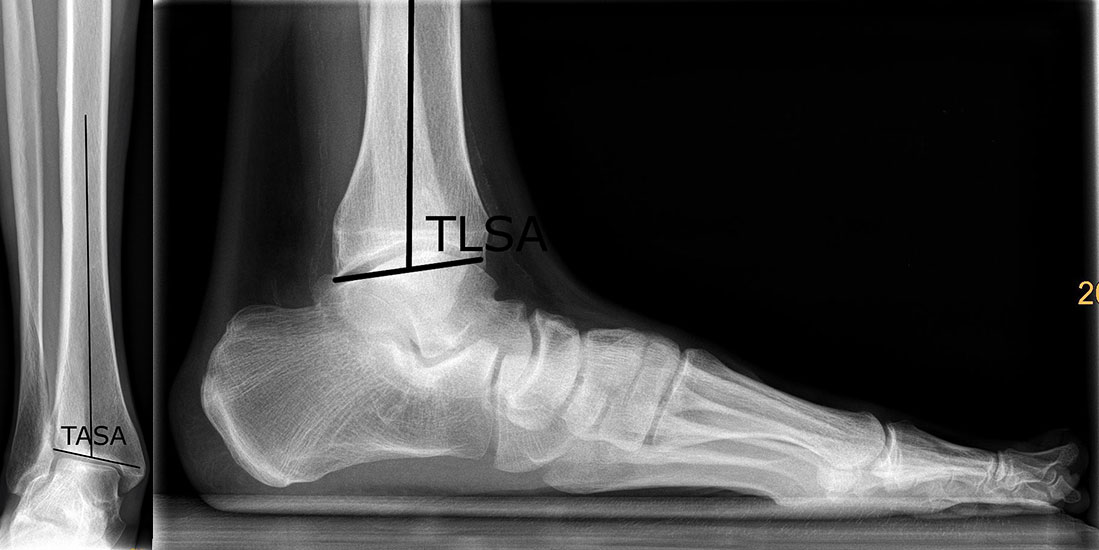

In der Standardröntgendiagnostik wird das Alignement unter Zuhilfenahme von 2 Winkeln bestimmt 3 (Abbildung 2):

• TASA (tibial anterior surface angle) - Winkel zwischen der Tibiaachse und der tibialen Gelenklinie im OSG ap Röntgenbild des oberen Sprunggelenks. Der Normalwert liegt bei 91-93° (32).

• TLSA (tibial lateral surface angle) - Winkel zwischen der Tibiaachse und der tibialen Gelenkfläche im OSG im seitlichen Röntgenbild oberes Sprunggelenk. Hier liegt der Normwert bei 81° +- 5°8.

Bestimmung des supramalleolaren Alignements: TASA (a) und des TLSA (b)

Abbildung 2